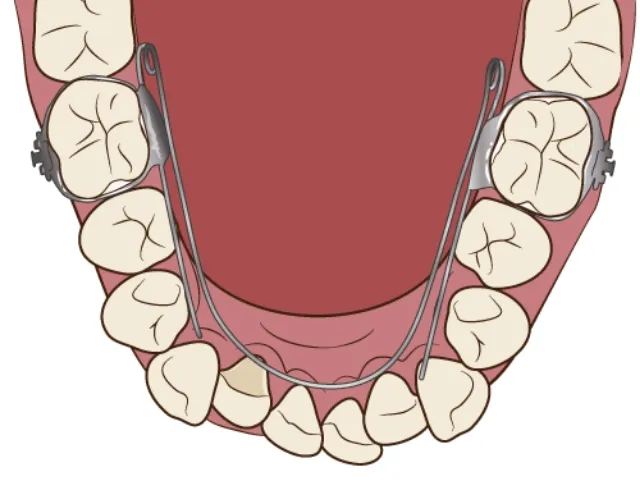

歯列矯正用ワイヤー

主に前歯数本の噛み合わせが逆になっているケースの改善で使用する装置です。左右の奥歯にバンドを固定し、それを支えとして歯列の内側に沿うようにワイヤーを通すことで、ワイヤーの弾力で特定の歯の傾斜を改善します。

反対咬合

| 診断名・主訴 | 前歯反対咬合 |

|---|---|

| 年齢・性別 | 12歳・男性 |

| 治療期間・回数 | 1年半 18回 |

| 治療に用いた主な装置 | リンガルアーチ(前方誘導弾線) |

| 抜歯部位 | なし |

| 治療費 | 35万円(税抜) |

| リスク・副作用 | 装置による違和感・疼痛・歯肉退縮・歯根吸収・虫歯のリスクなど |